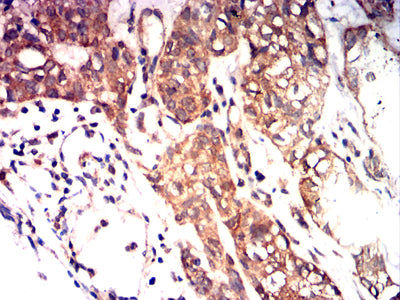

Immunohistochemical analysis of paraffin-embedded human Bladder cancer tissues using KITLG mouse mAb with DAB staining.